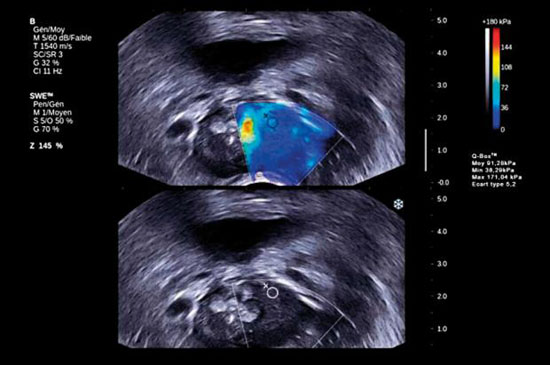

肿瘤并不像健康组织具有相同的弹性。弹性与血管的密度有关。肿瘤要比健康组织拥有更多的血管。而恶性肿瘤通常又比良性肿瘤有更多的血管和更大的血流量。

在癌症不同的发展阶段,不同的肿瘤有着不同的弹性。肿瘤也许比健康组织有更小或更大的弹性。一些肿瘤可能会扩散,而其它一些肿瘤则不会。换句话说,可以通过测量弹性获得器官和肿瘤的一幅全新的图画。

如果频率改变,声波的速度将会发生变化。事实证明,一种肿瘤越是危险,声波的速度就越快。要对这些声波做出解释,就需要具备大容量的计算能力。数学计算远非那么简单。

法国高等物理和化工大学(ESPCI)为法国超声波公司Supersonic Image使用这项技术提供支持,该大学教授迈克尔·坦特说:“在对乳腺癌的诊断中,弹性成像可以成为一种非常重要的补充检查手段。在不久的将来,我们将通过大规模临床试验,看看我们是否可以用弹性成像来取代乳房X线摄影术。”